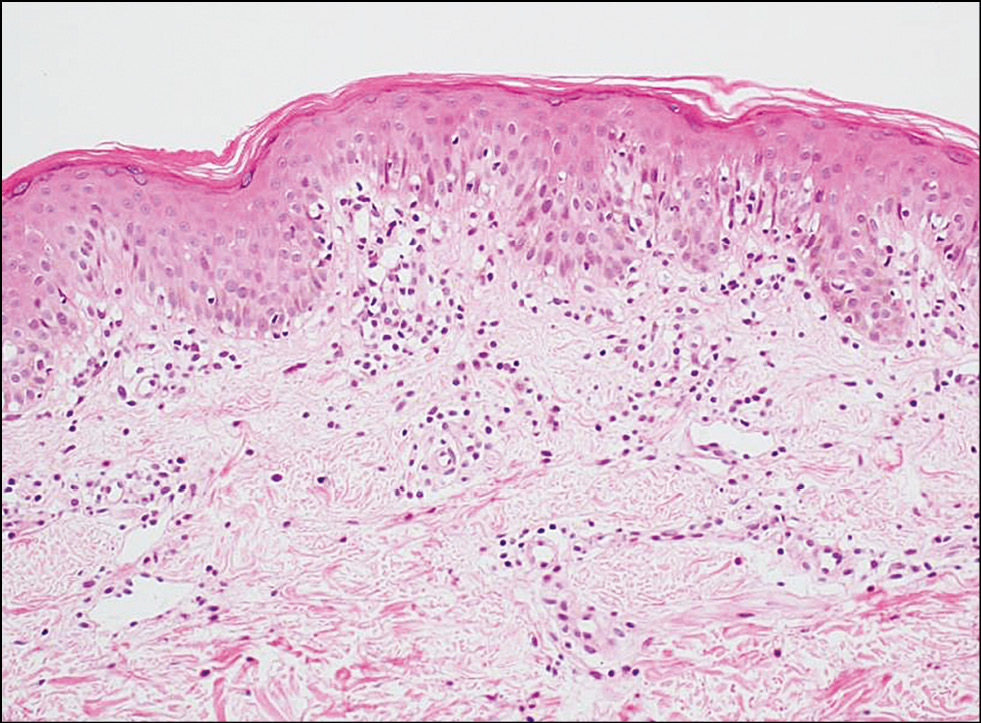

Третью группу составили 15 пациентов, из них 6 женщин и 9 мужчин в возрасте 42±4 лет, с диагнозом мелкобляшечного парапсориаза. Диагноз выставлен на основании следующих гистологических изменений: периваскулярный лимфоцитарный инфильтрат с примесью гистиоцитов, в эпидермисе фокальный гиперкератоз и паракератоз, у 2 пациентов обнаружен экзоцитоз лимфоцитов (рис. 8).

Рис. 8. Диагноз «Мелкобляшечный парапсориаз»: в эпидермисе наблюдается равномерный акантоз; в дерме ― интерстициальный инфильтрат, состоящий из лимфоцитов с примесью гистиоцитов, с тенденцией к проникновению в эпидермис (экзоцитоз). Окраска гематоксилином и эозином. ×100. / Fig. 8. The diagnosis is a small-plaque parapsoriasis. There is a uniform acantosis of the epidermis. There is a interstitial infiltrate consisting predominantly of lymphocytes with an admixture of histiocytes. Infiltrate have a tendency to penetrate the epidermis (exocytosis). (Hematoxylin & Eosin staining, ×100).